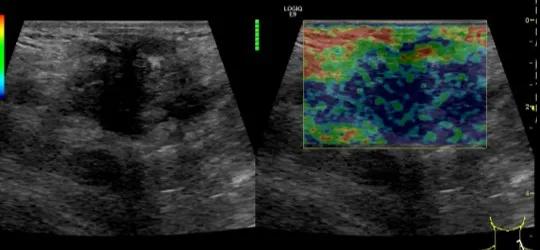

随后,徐栋教授进一步分享了五个临床实战病例,带来了更直观的热消融治疗经验。第一个病例是62岁肺癌患者,术后1年余发现双侧锁骨上淋巴结复发,侵犯神经,存在静脉回流、淋巴回流障碍,肿胀、疼痛非常明显。影像显示患者淋巴结边界不清、形态不规则,存在浸润,血流强化增强。由于患者在系统治疗后进展,且主要目的缓解症状、减瘤。局麻下行热消融术,从后向前逐层消融,热消融之后超声造影即刻评估显示完全充盈缺损,完全覆盖病灶。

(病例1图例)